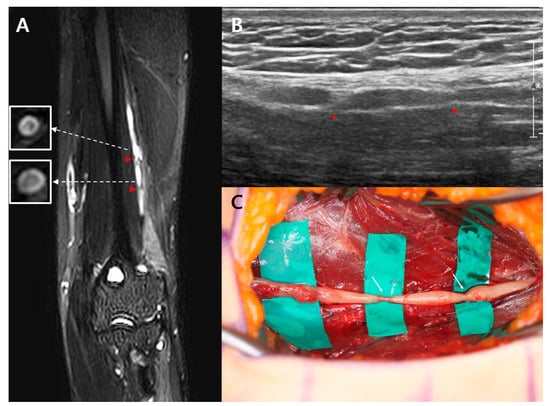

A 19-year-old man visited the department of physical medicine and rehabilitation at Samsung medical center because of a sudden onset of left wrist drop and sensory deficits in the dorsum of the left hand and wrist. A day before the onset of the wrist drop, he had experienced diffuse pain around the left elbow joint and posterior forearm that had persisted for a day. The symptom onset was spontaneous, with no identifiable cause, 5 months before presentation. A physical examination revealed complete paralysis of the left wrist and finger extensors and hypoalgesia, and hypoesthesia at the distal borders of the forearm and hand. An MRI, electrodiagnostic study, and ultrasound were performed 5 months after the symptom onset. A cervical MRI revealed no abnormalities. On NCS, the CMAP of the left radial nerve showed a lower amplitude compared to the right radial nerve (left side: 0.6 mV vs. right side: 8.7 mV). On needle EMG, positive sharp waves were generated in the left brachioradialis, extensor carpi radialis longus, extensor digitorum communis, and extensor indicis muscles. These muscles showed no MUAP during volitional activity. The NCS and EMG findings indicated radial neuropathy between the mid-humerus level and the elbow joint. A high-resolution 3-Tesla MRN, performed with the same protocol as case 1, revealed two focal constrictions of the left radial nerve 8.0 and 6.9 cm proximal to the lateral epicondyle, respectively, and distal to the radial groove. Additionally, the bull’s eye sign was observed juxta-proximal to the constrictions of the left radial nerve. A longitudinal ultrasound revealed two nerve constrictions in the areas corresponding to the constrictions observed on MRN (Figure 2B). Approximately 6 months after onset, the patient underwent surgery for interfascicular neurolysis. The intraoperative findings confirmed constriction, as observed on MRN, 8.0 cm proximal to the lateral epicondyle (Figure 2C). The second constriction site was also seen. However, at the 6-month postoperative follow-up, the patient’s motor weakness showed no improvement.

Figure 2. Case 2: (A) High-resolution magnetic resonance neurography reveals two focal constrictions (red arrowhead) of the left radial nerve 8.0 and 6.9 cm proximal to the lateral epicondyle, respectively. A bull’s eye sign (in white square) is observed juxta-proximal to each constriction site of the left radial nerve; (B) Longitudinal ultrasound reveals two constrictions (red arrowheads) of the left radial nerve; (C) Intraoperative findings confirm two constrictions (write arrow) of the left radial nerve.